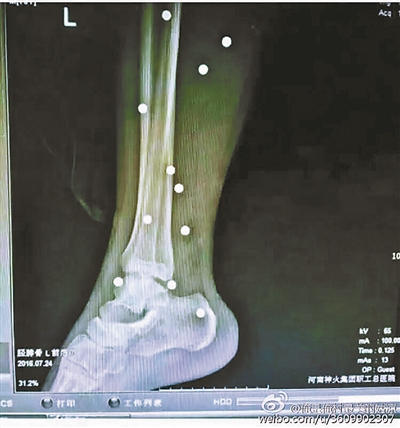

傷者體內(nèi)取出的鋼珠

爆炸導(dǎo)致鋼珠遍布傷者身體各處

黃明的伯伯對北青報記者表示,由于黃明直接踩到了爆炸物,所以傷情最為嚴(yán)重,“他的腿被炸斷,身體內(nèi)被炸進(jìn)了40多顆鋼珠。手術(shù)后已經(jīng)從體內(nèi)取出29顆鋼珠,還有十多顆鋼珠沒有取出來?!备鶕?jù)黃明的入院記錄,他全身有多處爆炸傷,且全身多處異物存留。

爆炸發(fā)生時,陳浩的位置與黃明靠得很近,因此也受傷較重。他告訴北青報記者,經(jīng)過10多個小時的手術(shù)后,醫(yī)生從他身體里取出了12顆鋼珠。目前,他和黃明兩人經(jīng)過手術(shù)后,已從重癥監(jiān)護(hù)室轉(zhuǎn)至普通病房。其余三人中,陳剛的臀部受傷,當(dāng)天晚上在醫(yī)院清理完傷口后便回了家,而同行的兩名女生身上有一些擦傷。